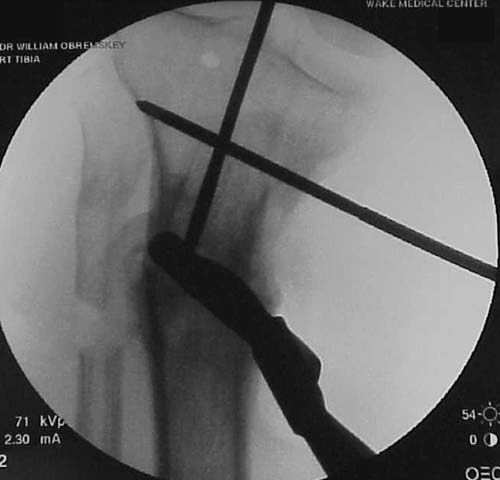

intraop